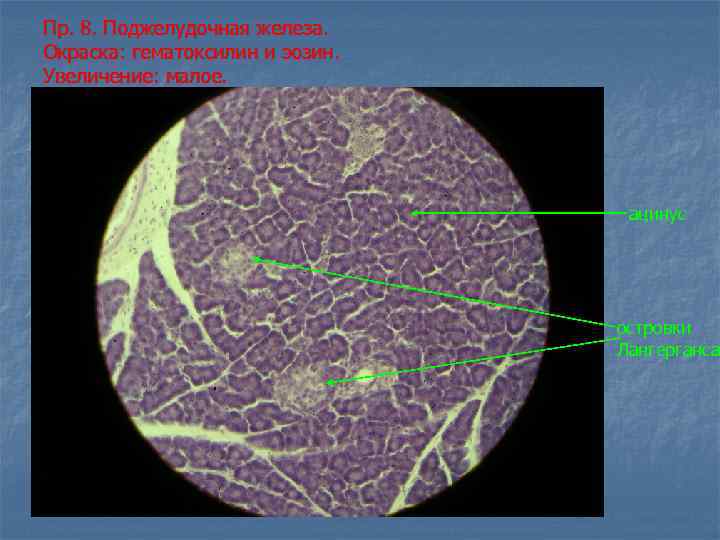

Пр. 8. Поджелудочная железа. Окраска: гематоксилин и эозин. Увеличение: малое. островок Лангерганса ацинус междольковый выводной проток прослойки соединительной ткани междольковые сосуды

Пр. 8. Поджелудочная железа. Окраска: гематоксилин и эозин. Увеличение: малое. ацинус островки Лангерганса